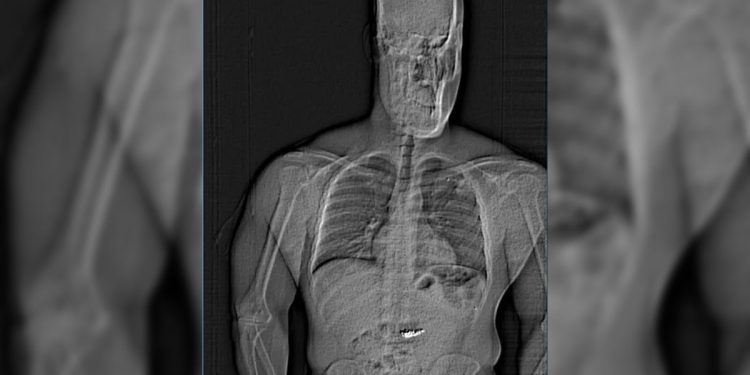

Naušnice su se kasnije pojavile na skeniranju tijela snimljenom u zatvoru u okrugu Orange, izjavila je izjava o uhićenju.